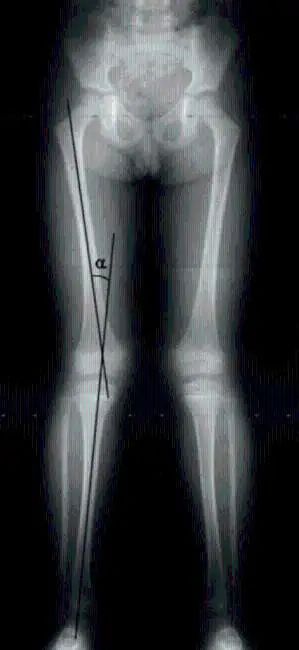

“X型腿”其实是一种状态。当我们用肉眼观察时,站立时我们的腿呈X形。

膝外翻是X形腿的真正医学名称。站立时,如果膝盖并拢而脚踝不能并拢,这就是膝盖外翻。